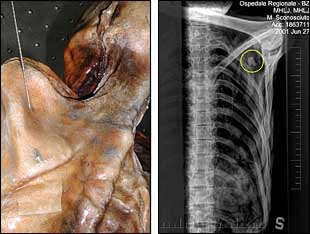

Ötzi, el hombre de los hielos, la momia de la edad del bronce -5.300 años de antigüedad- encontrada en 1991 en un glaciar de los Alpes tiroleses, en la frontera entre Italia y Austria, murió de un flechazo. Un equipo del Museo de Arqueología del Sur del Tirol, en Bolzano (Italia) -construido para albergar ese hallazgo antropológico-, ha resuelto el enigma del fallecimiento, y especificó que habían radiografiado la punta de la saeta bajo el hombro izquierdo.

Hasta ahora, unas teorías especulaban que murió de frío, y otras, que había sufrido una caída. El radiólogo Paul Gostner afirmó ayer que se puede reconstruir la trayectoria de la flecha a través de los huesos, y que la muerte se habría producido a las pocas horas del impacto.